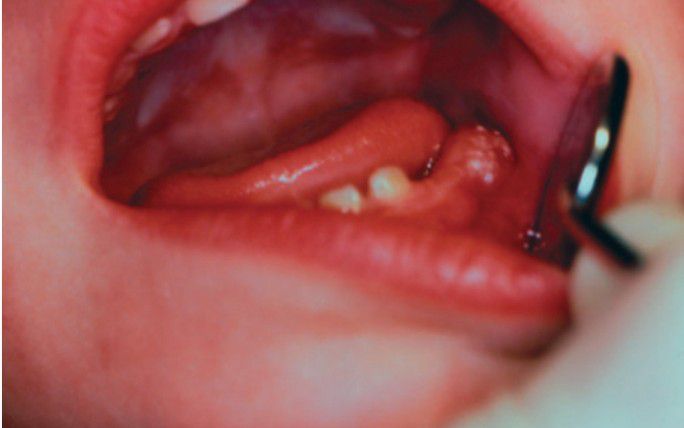

Bohn's nodules

Gingival cysts of the newborn in a 2-year-old with retained teeth. These cysts appear as clusters of pearly white papules on the crest of the ridge in the mandibular molar area.